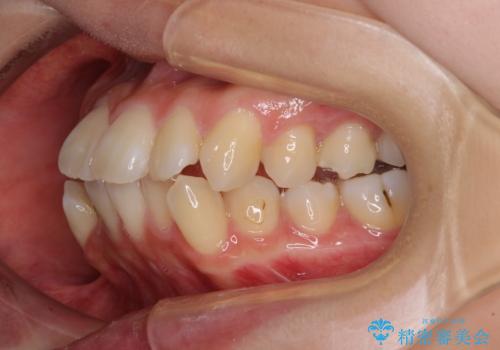

【モニター】口が閉じにくい 抜歯矯正で口元を引っ込める

- 前歯のデコボコや口元の突出感、口の閉じにくさを気にして来院された患者様です。

上下左右第一小臼歯4本を抜歯し、ワイヤー装置にてデコボコを解消しながら口元を引っ込めるよう矯正治療を行うこととしました。

抜歯スペースを閉じている過程で、左側の上下犬歯が引っかかってしまい、進捗が停滞しましたが、当初予定の2年~2年半の間で無事に治療を終えることができました。